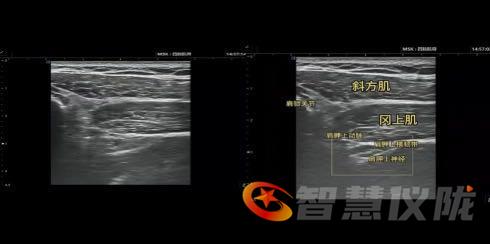

这项技术借助高清超声,医生可动态观察神经、血管与肌肉的精细结构,将药物或射频针毫米级精准送达病灶,避免损伤周围组织。其核心优势在于:

1.诊断即治疗:通过阻滞效果验证疼痛来源。

2.安全微创:可视化操作降低血管、脏器损伤风险。